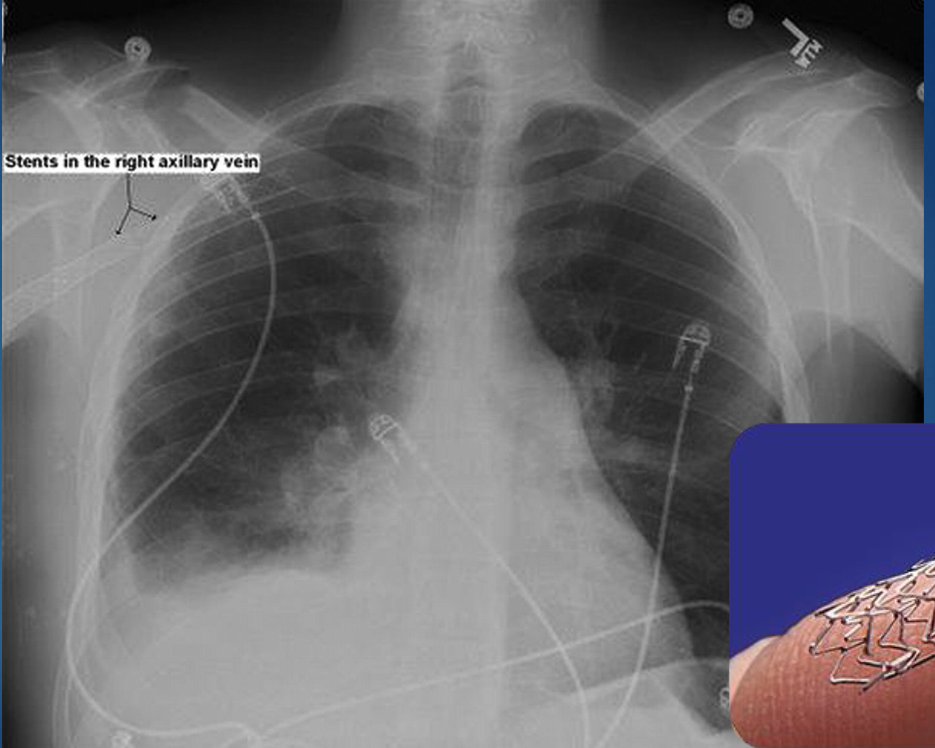

how do stents appear on xray?

bright, metallic, tubular/cylindrical mesh structures

what is cardiac balloon angioplasty and stenting?

when a balloon tipped catherter is inserted in artery

balloon is inflated to flatten plaque & expand artery

mesh tube/stent is placed to keep artery open